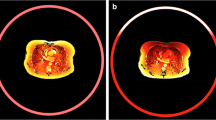

Shielded images in Fig. 1 illustrate beam-hardening artefacts caused by bismuth shielding; they are most noticeable for the breast shield. Measurement of noise in the images demonstrated the expected increase of noise in images that were affected by shielding (Fig. 2). The increase of noise by the relatively small eye shield was only modest (Fig. 2a) whereas the increase in noise introduced by the thyroid shield and breast shield was more prominent (Fig. 2b). The increase in noise caused by the breast shield made noise in the shielded images dominant compared with adjacent images in the range of a typical chest scan. A subsequent evaluation aimed at translating a theoretical reduction of tube current and the associated proportional reduction in organ dose and total energy imparted into an increase in noise within the unshielded images. To achieve this, a linear regression between tube charge and the inverse of the square noise was derived. A good correlation was found (raverage=0.985). A y-intercept larger than zero was found, indicating a substantial contribution of other sources of noise than quantum noise (e.g., equipment noise) at very low doses, i.e., doses well below the range considered in this study.

Image noise measured with and without eye-lens shielding for the computed tomography (CT) brain scan. a Arrow indicates increased noise in shielded images (closed dots) and b noise with and without thyroid or breast shield for a CT chest scan. The arrow pointing at closed dots indicates increased noise due to thyroid shielding; the two arrows pointing at closed dots indicate increased noise due to breast shielding; the single arrowhead indicates the range of breast modules. The thin line in b corresponds with a 10.3% reduction of tube current and thus represents an acquisition yielding the same energy imparted as the shielded acquisition, showing a much lower noise level within the shielded range. The thin dotted line in b corresponds with a 30% reduction of tube current and thus represents an acquisition yielding the same breast dose as the shielded acquisition, showing a lower noise level within the shielded range. A sagittal reformat covering only part of the phantom and bismuth shields is shown in b

Bismuth shielding resulted in a slight reduction of total energy imparted to the anthropomorphic phantom for the CT brain (1.7%), CT cervical spine (5.8%), and CT chest (10.3%) scans. This reduction can, of course, also be achieved by an equal percentage decrease of tube current. This would cause a modest, almost unnoticeable, increase of image noise within the entire scanned range, an increase by less than 1% (CT brain), less than 3% (CT cervical spine), and about 5.5% (CT chest), respectively (Fig. 2b).

The breast shield markedly reduces dose to the breasts (30%) and the lungs (15%) but at a substantial increase of noise in the shielded images and at the cost of mild beam-hardening artefacts. Without breast shielding, relatively modest image noise was observed in the scanned range containing the breasts; with breast shields, noise became dominant in this—for diagnosis, most relevant—range compared with the adjacent imaged range within the lungs but outside the shielded range. Breast shielding reduced total energy imparted during the CT chest scan by 10.3%, a slightly higher noise level, i.e., 5.5% higher but for the radiologist still unnoticeable, and this would result if tube current have been reduced by the same percentage (Fig. 2b).

Theoretically, reduction of tube current by 30% could be implemented as an alternative to bismuth shielding to achieve an equal dose reduction for breast tissue during an unshielded chest scan while yielding better image quality compared with shielded acquisition. This is because the associated increased image noise at a 30% reduction of tube current remains well below noise observed within the shielded acquisition, except for the diagnostically less relevant shoulder region where the noise just reaches a level comparable with noise within the shielded range (Fig. 2b).